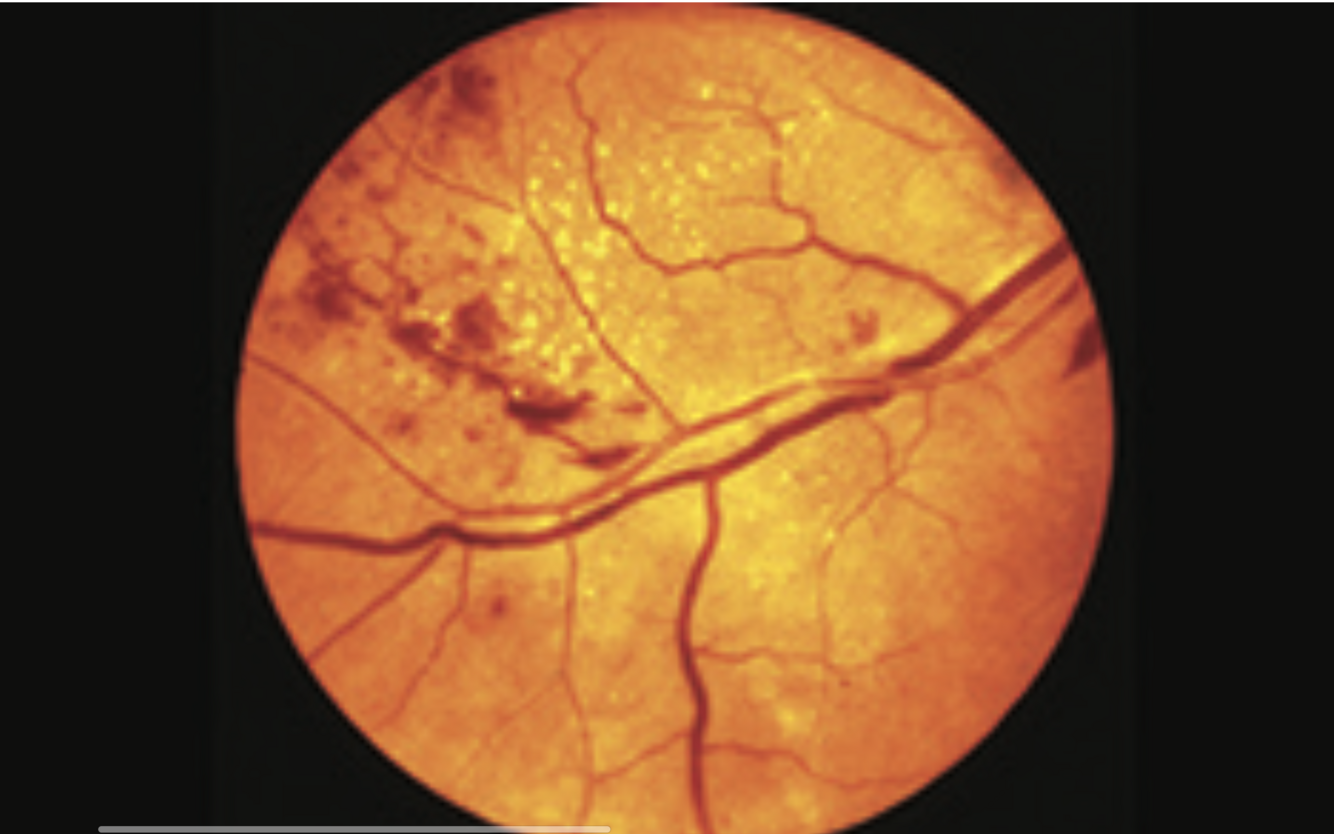

Diabetic Maculopathy

- hard exudates in macular area

- flame haemorrhages and microaneurysms